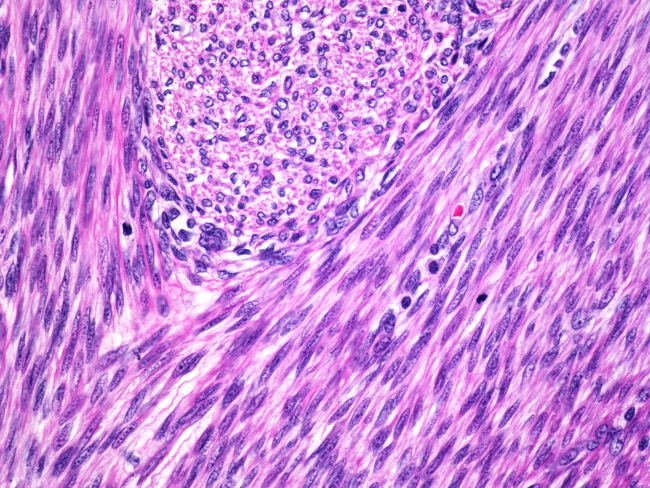

leiomyoma uterine pathology microscopic cellular dissecting leiomyomas variants mitotically bizzare nuclei epithelioid lipomatous myxoid hydropic include ilovepathology

uterus leiomyoma histology uterine uteri stepwards cat pathology cells normal figure fibroid female muscle analysis smooth resemble bmj

leiomyoma uterus histopathology

leiomyoma pathology outlines uterine muscle intravenous smooth pathologyoutlines growth lymphangioleiomyomatosis microscopic